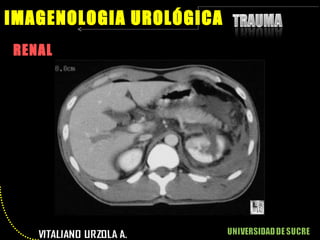

RENAL IMAGENOLOGIA UROLÓGICA